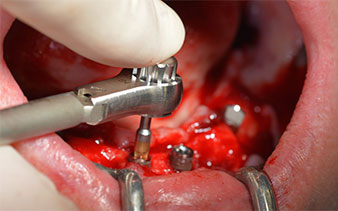

After removal of the residual dentition in the mandible, the alveolar crest was exposed from 37 to 47.

The mental foramen was first identified as a limiting anatomical structure and then the cortical bone of the crest was smoothed with the straight handpiece and a large rose-head bur (Fig. 4).

residual dentition

Fig. 4